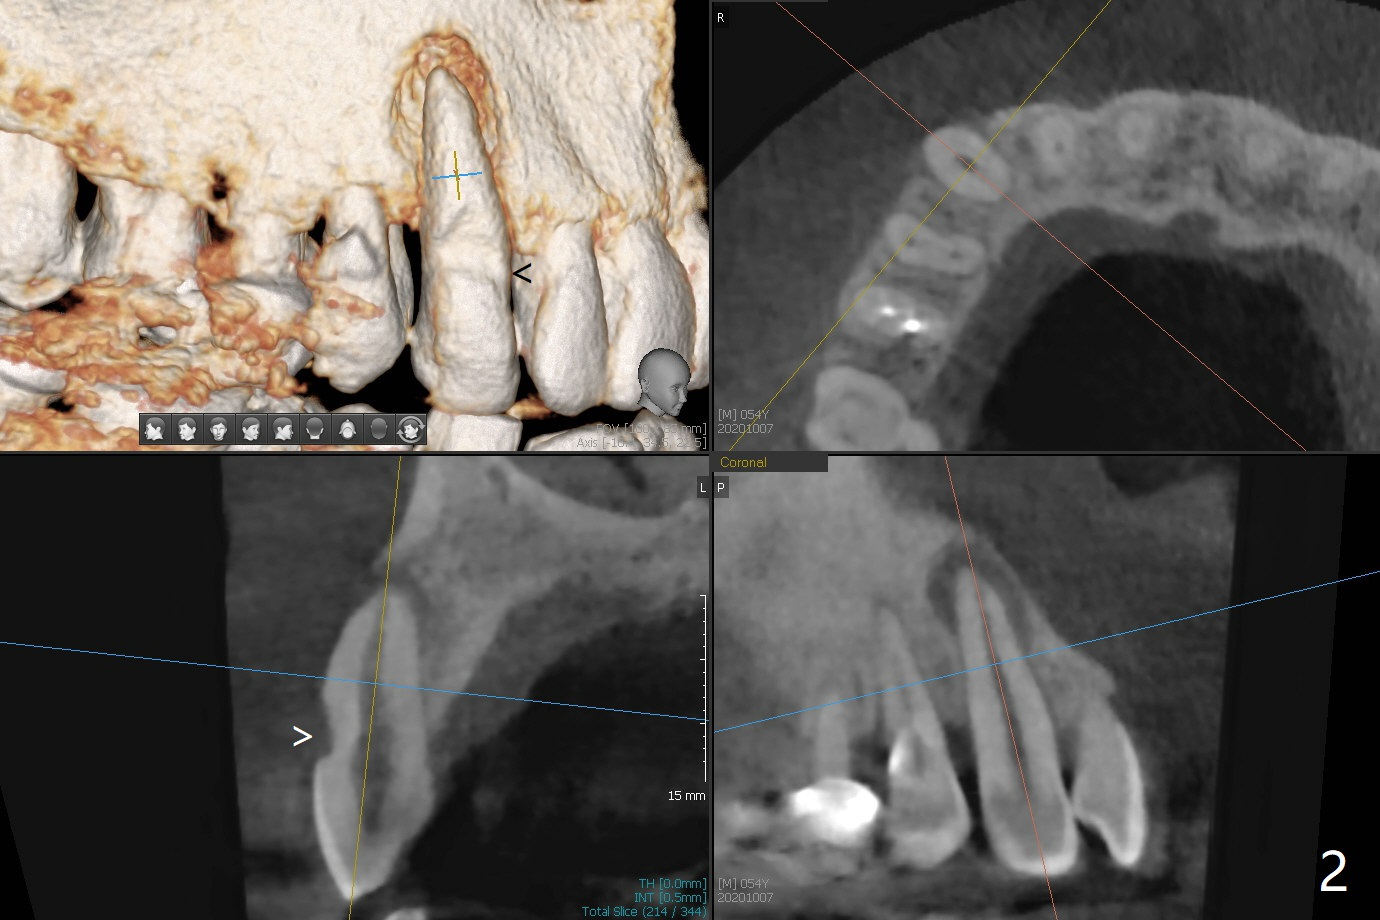

54岁男牙齿问题好像与牙周病和咀嚼力大有关(图一),虽然右上3(图二)和左下6(图三,四)需要治疗,因为疼痛他要求先处理左上6(图五)。后者腭侧根骨质吸收严重,植体尽量颊侧植入(图六),4.5 或者5.0x11毫米。放置粘性骨粉至植体平台,为了简化术中基台放置,使用Non-Hex Temporary Abutment,临时牙冠做的尽量大,占据牙槽窝空间,最后将PRF膜塞入两者之间。Return to Prevent Molar Periimplantitis (Protocols, Table) No Deviation No Caries Metronidazole CT/前牙植牙 Socket Shield Xin Wei, DDS, PhD, MS 1st edition 10/11/2020, last revision 02/21/2021